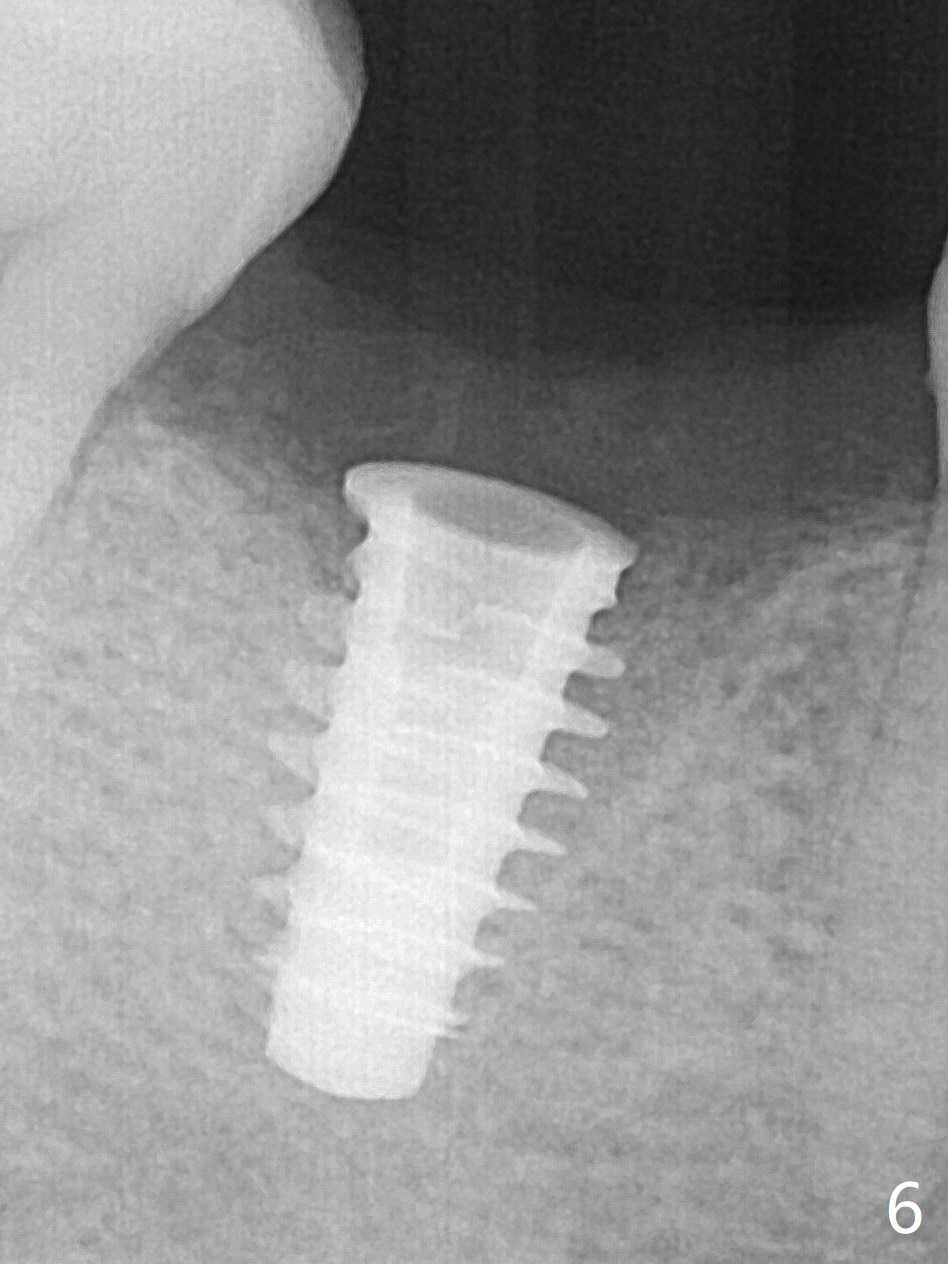

After removal of the residual roots at #30 (Fig.1), a thin septum (Fig.2 *) is removed with Rongeur (Fig.3). Following use of 4.8 mm Magic Drill, a 5x9 mm dummy implant is placed (Fig.4). To reduce socket gap (*), a 6 mm IBS implant is inserted with >50 Ncm (Fig.5). What is unexpected is heavy reduction in the height of a 6.5x4(3) mm abutment (A) because of the short crown height of the lower posterior teeth (Fig.1) and supraeruption of the tooth #3. The immediate provisional is unstable postop. The remade one dislodges soon, so does the abutment (Fig.6, 3 months postop). It appears that bone pattern in the distal socket changes.